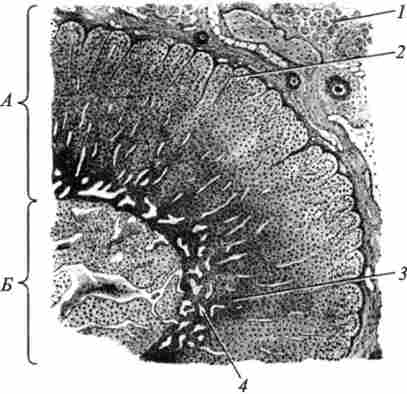

У кірковій речовині розрізняють клубочкову, пучкову, сітчасту зони (рис. 77).

РНС. 77. Будова надниркової залози:

А - кіркова речовина; Б - мозкову речовину; / - сполучнотканинна оболонка; 2 - клубочковая зона; 3 - пускова зона; 4 - сітчаста зона